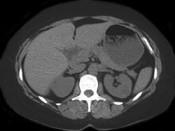

问题 女性,最近感腰部胀痛,体检发现B超右肾正常,左肾有一囊肿,双肾体积不增大,尿常规、肾功能正常,无家族病史,CT表现入图所示,最可能考虑为 ( )

选项 A.肾积水 B.多囊肾 C.多发性肾囊肿 D.肾肿瘤 E.肾结核

答案 C